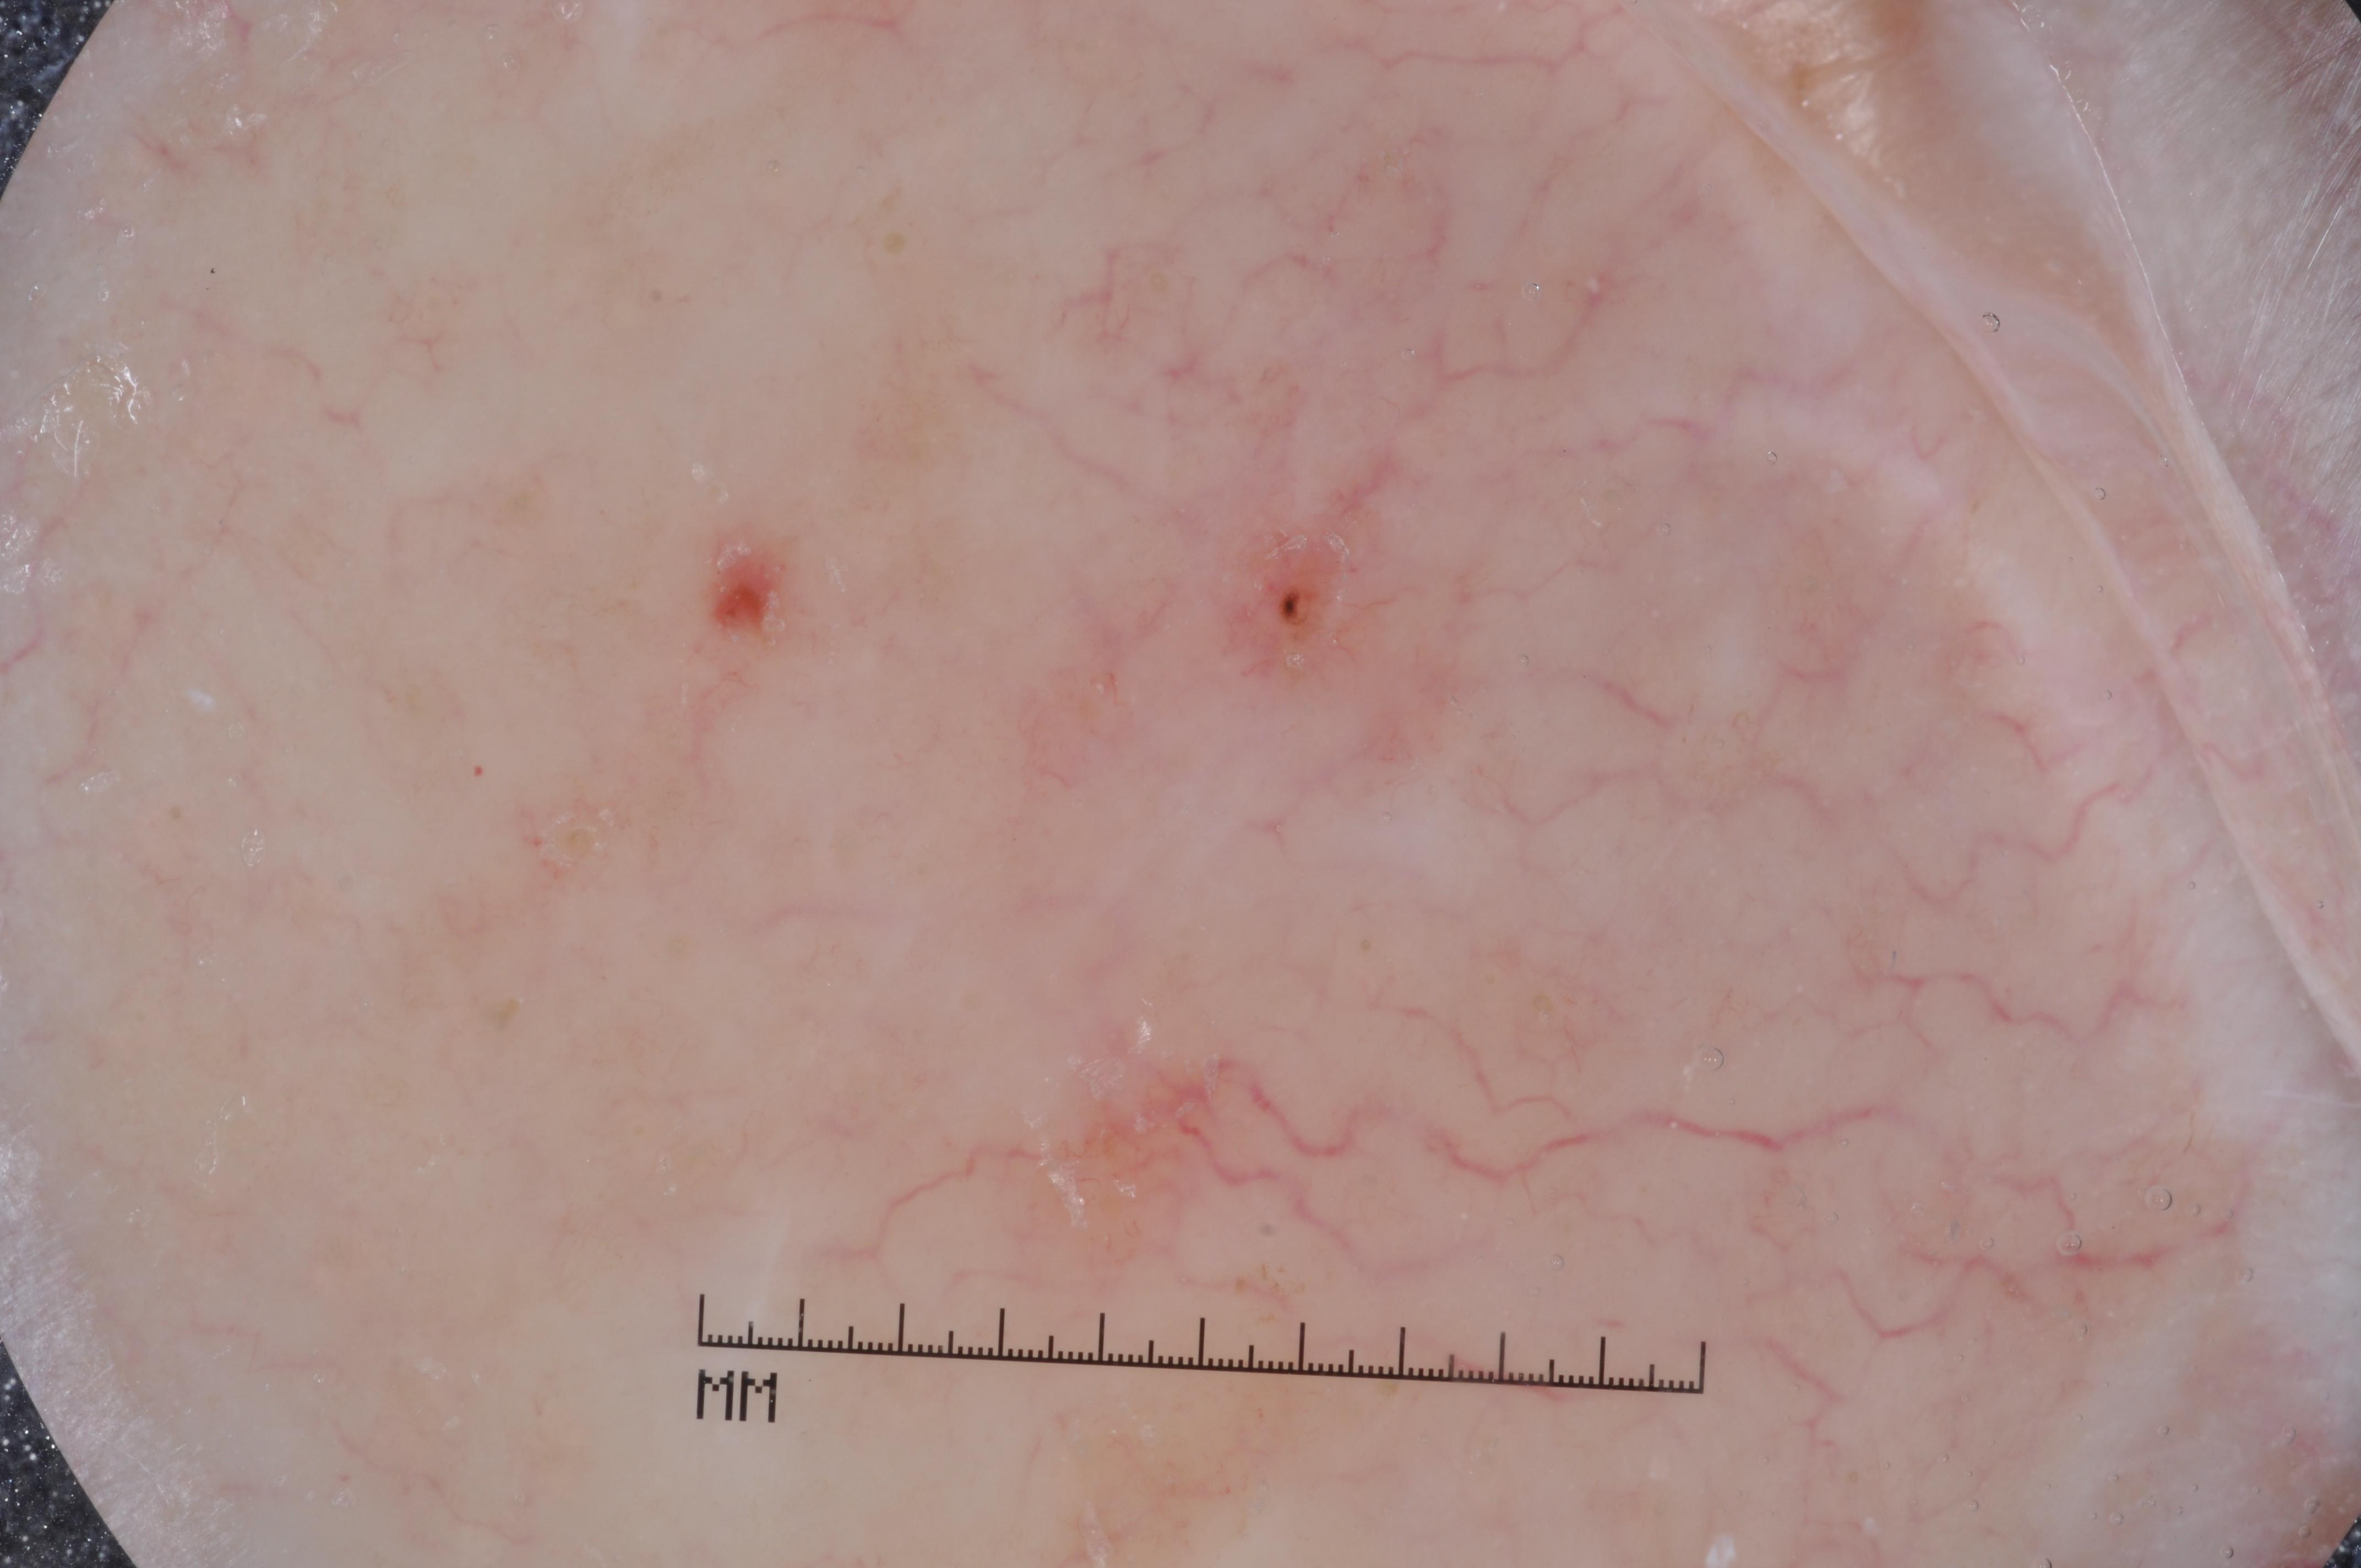

{

"age_approx": 60,

"anatom_site_general": "upper extremity",

"concomitant_biopsy": true,

"dermoscopic_type": "contact non-polarized",

"diagnosis_1": "Malignant",

"diagnosis_2": "Malignant adnexal epithelial proliferations - Follicular",

"diagnosis_3": "Basal cell carcinoma",

"diagnosis_confirm_type": "histopathology",

"image_type": "dermoscopic",

"lesion_id": "IL_8774044",

"melanocytic": false,

"sex": "male"